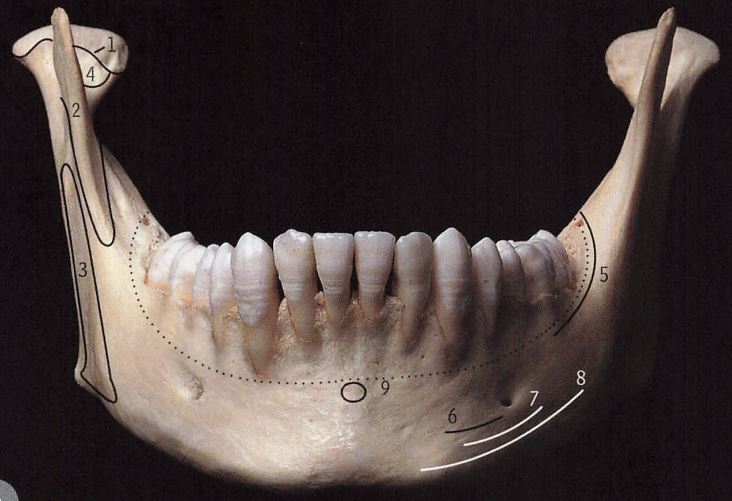

- 下颌骨是什么样的

下颌骨包括下颌体和双侧下颌支。所以我们看下颌骨有这么几个维度:横向、垂直向、前后向。

1、宽度/横向

这个宽度就决定了我们在看一个人的时候,是国字脸、鹅蛋脸、圆脸、长脸。这个和下巴尖不尖不是一个维度的事情。

2、下颌角角度/垂直向

下颌角角度就是下颌体和下颌升支所成的角度。这个角度代表了侧面看一个人的轮廓,是有一个轮廓清晰的下颌角,还是一个柔和不显眼的下颌角。我们把下颌角度平的称为低角,把下颌角度陡的称为高角,把下颌角度正常的称为均角。

但是这两个维度是有联系的。一般来说,下颌角角度小的,脸短,脸方。下颌角角度大的,脸长。下颌角的角度是由基因决定的,其次还受咬肌力量大小的影响。如果咬肌力量大,就倾向于肌肉把下颌骨使劲往上拉,让下颌角角度变小,同时脸变短。如果肌肉力量不足,下颌角角度就会偏大,同时脸变长。

3、下颌的突缩、颏部的突缩/前后向

很多人都在说自己有没有下巴,有没有下巴怎么看呢?要把头位摆正,眶耳平面(眼眶最低点和外耳道最上点形成的平面)平行于地面,看下颌骨相对于上颌骨的突缩情况。这个人的下颌骨明显在上颌骨的后方,这个就叫做下颌后缩。如果下颌骨在上颌骨前方,那就叫下颌前突。如果下颌骨和上颌骨前后向基本一致,就是标准的下颌位置。(这是在上颌骨正常的情况下判断下颌骨,但是也存在上颌前突等各种情况,此为了说明方便特此简化上颌的问题,单说下颌。)

很多人问自己嘴突是牙性还是骨性。牙性就是指上下颌骨前后向基本一致,但是牙齿前突。骨性就是指上颌前突或者下颌后缩,而尤其以下颌后缩为主要原因。

以上说的是下颌的突缩,还有颏部的突缩。颏部特指下颌联合最前部最突出的区域,这个区域是人类特有的,而其他灵长类是没有的,想想猩猩猴子的动物,他们都没有颏部。有了颏部就会有颏部上方的凹陷,叫做颏唇沟。颏部越突,颏唇沟越凹陷,越显得有下巴。

有的人下颌后缩,但是颏部发育得很好,就不显得下颌后缩。而有的人下颌后缩也伴随了颏部后缩,侧面看就会非常明显“没下巴”。